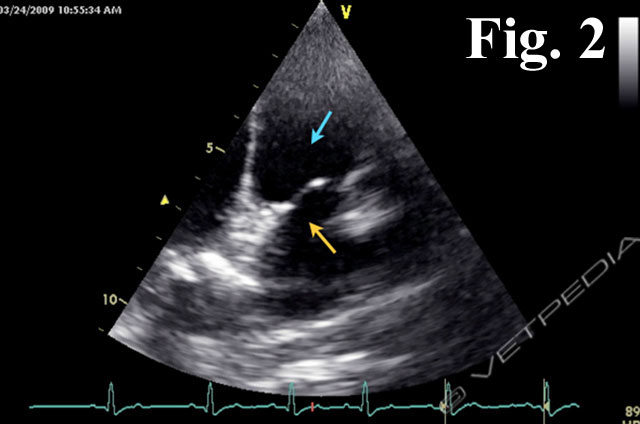

{{/_source.additionalInfo}}Nel cuore di riconosce uno specifico sistema di conduzione deputato a generare e condurre l’impulso elettrico al miocardio di lavoro. Tale sistema si compone di cellule in grado di generare l’impulso elettrico in maniera spontanea e di strutture rappresentate da fasci che propagano lo stimolo agli atri ed ai ventricoli. L’impulso elettric...